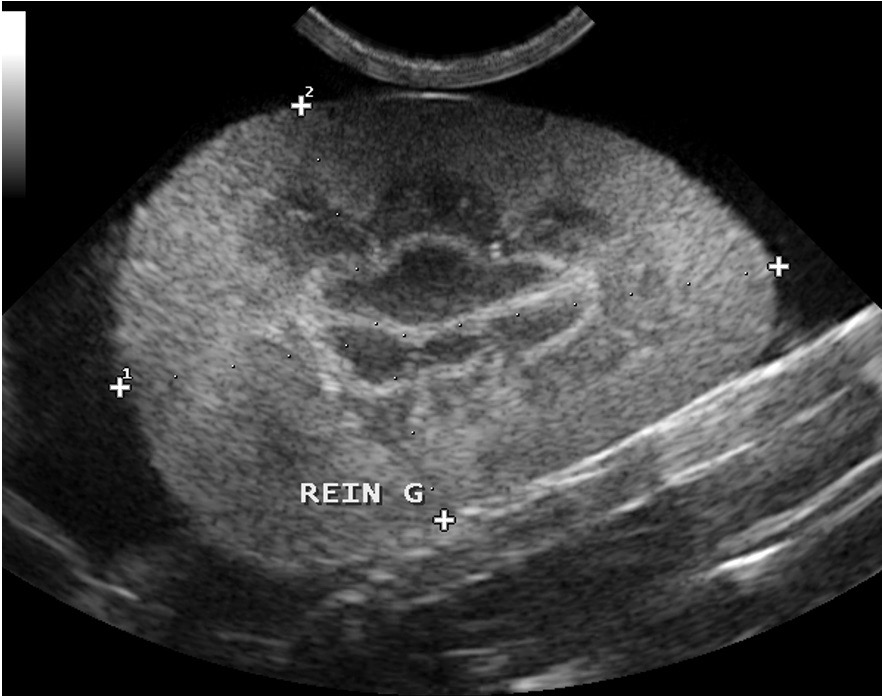

Deux images d’ascite importante chez des chats atteints de PIF : à gauche, seule la mince paroi de la vessie permet de distinguer le liquide à l’intérieur (l’urine) du liquide à l’extérieur (l’ascite). A droite : un rein perdu au milieu du liquide d’ascite ; on remarquera au passage la corticale rénale hyperéchogène, et aussi la présence d’un anneau médullaire (ou « medullary rim », cette ligne hyperéchogène qui suit la jonction cortico-médullaire) marqué : dans une étude portant sur la signification de cette image échographique dans le rein des chats (Ferreira & Coll, 2020), sur 23 chats atteints de PIF, 15 présentaient cet anneau médullaire, le plus souvent épais, et 8 ne le présentaient pas. Pour les auteurs, cette différence permet de conclure à une association significative entre anneau médullaire et PIF. Donc un indice diagnostique intéressant mais bon, ce n’est pas parce qu’on voit un anneau médullaire dans le rein d’un chat que celui-ci a forcément la PIF, et réciproquement !